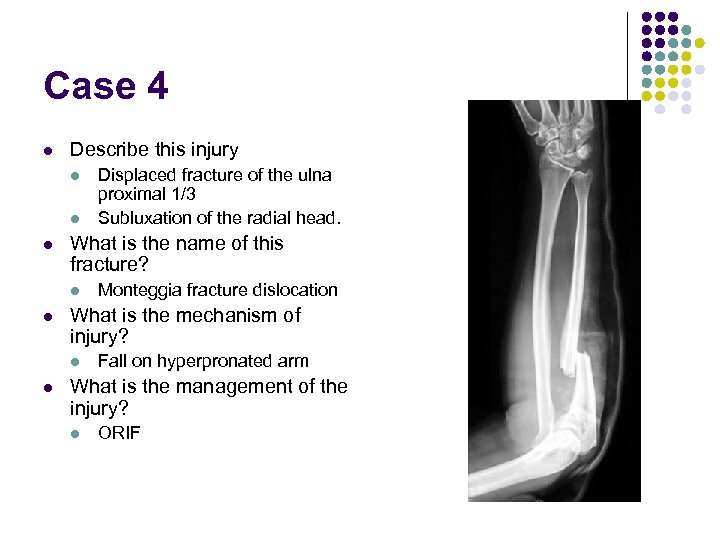

Case 4 l Describe this injury l l l What is the name of this fracture? l l Monteggia fracture dislocation What is the mechanism of injury? l l Displaced fracture of the ulna proximal 1/3 Subluxation of the radial head. Fall on hyperpronated arm What is the management of the injury? l ORIF